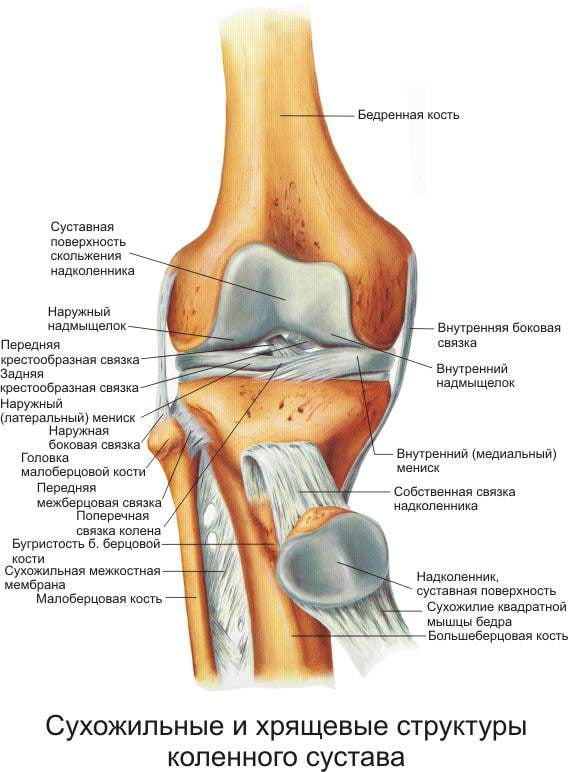

Тендинит

Тендинитом называют воспалительное поражение сухожилий с их последующей дегенерацией. В процесс вовлекается собственная связка надколенника. Патологией страдают в основном спортсмены и лица, ведущие активный образ жизни. Тендинит считается профессиональным заболеванием футболистов, теннисистов, баскетболистов, легкоатлетов и т. д.